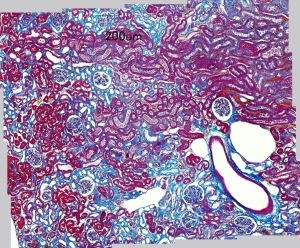

マウス腎臓糸球体のタコ足細胞(パラフィン切片)

(電顕支援 尾山研究員)